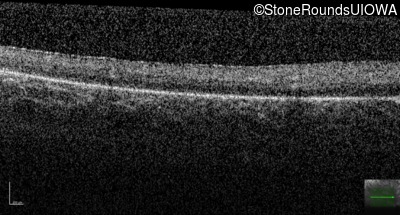

Optical Coherence Tomography - Left - Hand Motion sc

Exemplar